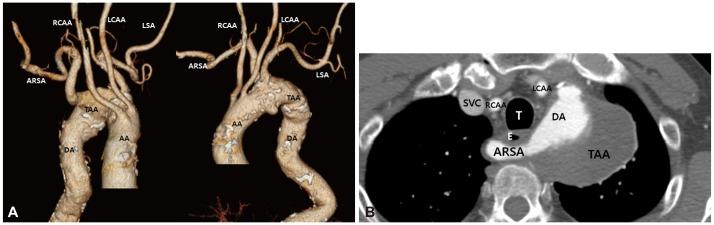

An aberrant right subclavian artery (ARSA) is the most common vascular abnormality of the aortic arch and is associated with development of aneurysms in 3-8% of these anomalies. In this case report, we describe an 84-year-old man with a symptomatic ARSA treated with staged hybrid procedure combining surgical replacement of the ascending aorta and bilateral carotid-to-subclavian artery bypass with implantation of a stent graft in the aortic arch and descending aorta. Our case suggests that a less invasive hybrid therapy can be performed successfully for the treatment of ARSA with aneurysmal change in patients at high surgical risk.

异常右锁骨下动脉(ARSA)是主动脉弓最常见的血管异常,在这些异常中,有 3-8%会发展为动脉瘤。在本病例报告中,我们描述了一位 84 岁的男性患者,他患有症状性 ARSA,接受了分期杂交手术治疗,该手术结合了升主动脉置换术和双侧颈动脉-锁骨下动脉旁路术,并在主动脉弓和降主动脉中植入了支架移植物。我们的病例表明,对于高手术风险的患者,一种微创的杂交治疗方法可以成功地用于治疗伴有动脉瘤样改变的 ARSA。